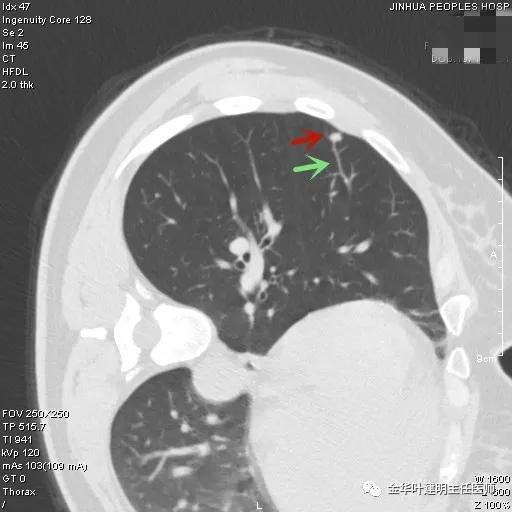

上图示结核。我们发现其有明显的卫星灶,如绿色箭头所示,主病灶处也是周边有模糊区域,病灶整体密度较为均匀(肿瘤容易生长不均致密度欠均匀,显杂乱)。